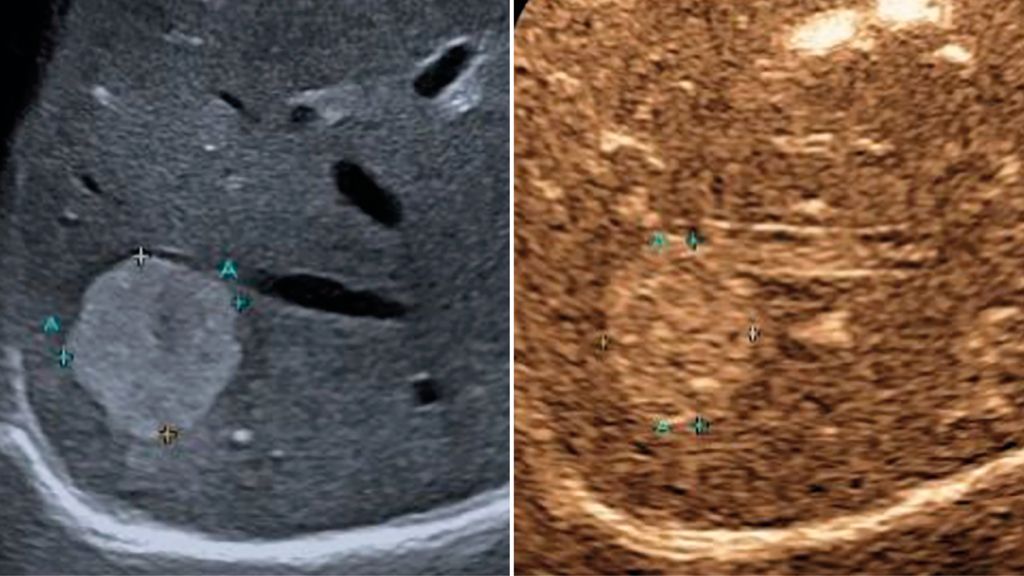

Trotz der hohen Aussagekraft moderner Ultraschallgeräte im B-Mode kann derzeit – mit Ausnahme des Screenings auf hepatozelluläre Karzinome bei chronischen Lebererkrankungen – kein generelles Leberscreening empfohlen werden.5 Die Mehrzahl fokaler Leberläsionen ist benigne, darunter fokale Steatosen, Zysten, Hämangiome oder fokale noduläre Hyperplasien (Abb.3). Maligne Raumforderungen sind in populationsbasierten Studien selten.6

Abb. 3: Darstellung einer fokalen nodulären Hyperplasie (FNH) in der arteriellen Frühphase nach Gabe von 1,2ml SonoVue® mittels CEUS (links) und in der mikrovaskulären Bildgebung (Canon®-superb «Microvascular imaging»-Modus), wo die Radspeichenstruktur besser zur Darstellung kommt

Interventionelle Lebersonografie

Neben den nichtinvasiven Verfahren bleibt die sonografisch gesteuerte Leberpunktion ein etablierter Bestandteil der diagnostischen Abklärung fokaler und diffuser Lebererkrankungen. Die Echtzeit-Bildführung ermöglicht eine präzise Nadelplatzierung und reduziert das Risiko von Komplikationen. Darüber hinaus dient die Sonografie als Navigationsverfahren für therapeutische Eingriffe, insbesondere für die perkutane Mikrowellenablation von Lebertumoren, die eine minimalinvasive Behandlungsalternative zur chirurgischen Resektion darstellt.19